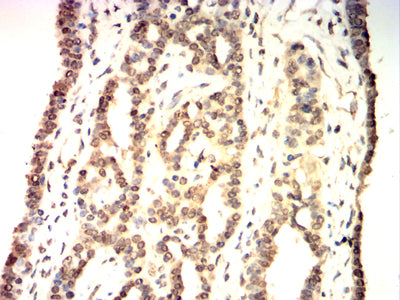

Immunohistochemical analysis of paraffin-embedded human cervical cancer tissues using XRCC1 mouse mAb with DAB staining.